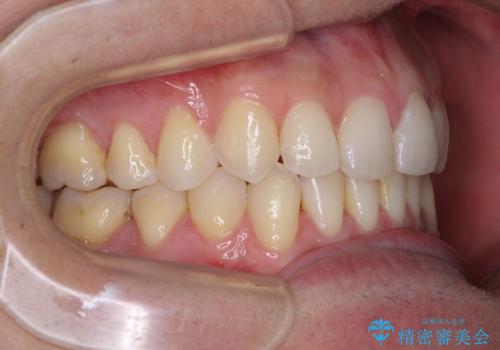

ディープバイトと叢生 インビザラインによる矯正治療

- 前歯のディープバイトと叢生を気にして来院された患者様です。

目立ちにくい装置を希望されていたため、ワイヤー装置とインビザラインを提案したところ、インビザラインを希望されました。

上下ともに叢生が認められたため、親知らずすべてを抜歯し、歯列全体を後方へ移動させることで歯列を整えることとしました。

上顎奥歯の銀歯も気になっていたので、矯正治療の途中でセラミッククラウンへ変更し、その後歯列を仕上げていくこととしました。

ディープバイトもデコボコも改善され、気になっていた銀歯もセラミックとなり、患者様には大変満足していただきました。